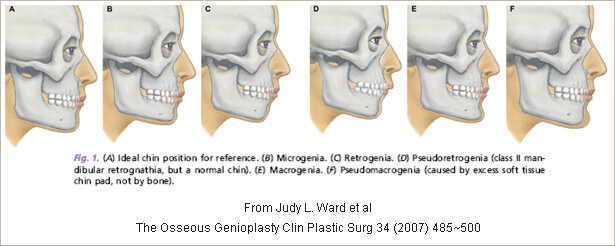

3D / 3 Vector / 3 Dimensional Genioplasty includes: Altering the 3 Dimensions of the chin, meaning - Width, Height, Projection. These are the measurments im gonna change in this surgery:

- Projection: +4mm

- Height: +3.5mm

- Width: +4.3mm

3D / 3 Vector / 3 Dimensional Genioplasty includes: Altering the 3 Dimensions of the chin, meaning - Width, Height, Projection. These are the measurments im gonna change in this surgery:

- Projection: +4mm

- Height: +3.5mm

- Width: +4.3mm